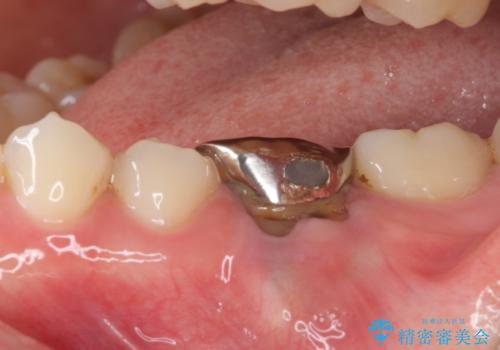

奥の銀歯も気になっていたため、矯正治療後にセラミッククラウンにて補綴することとしました。